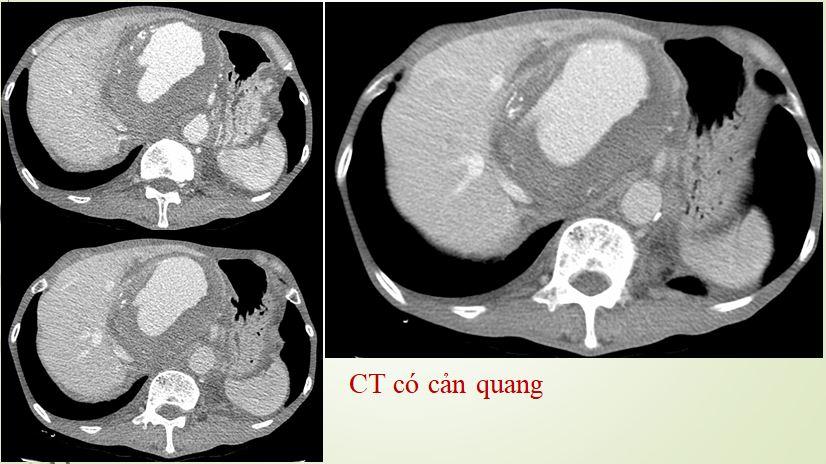

Hình CT có gì đó bất thường ở thận phải, chưa biết có liên quan tới chấn thương cũ hay không vì bệnh nhân không ghi nhận tiểu máu. Đây là điều bất thường vì đa số các vấn đề: bướu máu trong thận, rò động tĩnh mạch thận sau mổ nội soi, ung thư trong thận thường gây chảy máu, và bệnh nhân sẽ thấy tiểu ra máu

Hình ảnh DSA cho thấy có một vị trí thông động tĩnh mạch, làm cho lưu lượng tưới máu đến nhu mô thận giảm đáng kể, từ đó có thể giải thích tại sao bệnh nhân tăng huyết áp dù tuổi còn trẻ Kết quả siêu âm bụng tổng quát không ghi nhận bất thường, siêu âm động mạch thận: Nghi ngờ rò động mạch thận. Xét nghiệm máu trong giới hạn bình thường. Bác sĩ chẩn đoán: tăng huyết áp người trẻ – rò động tĩnh mạch thận. Câu hỏi đặt ra cho các bác sĩ là phải làm gì? Nếu can thiệp không thành công thì phẫu thuật, nhưng năm 2006 phẫu thuật thận cũng rất khó khăn. Các bác sĩ quyết định cố gắng can thiệp nội mạch, dùng keo, dùng bóng, dùng tất cả phương tiện có trong tay lúc đó, cuối cùng đã bít được chỗ thông nối động mạch thận và tĩnh mạch chủ.